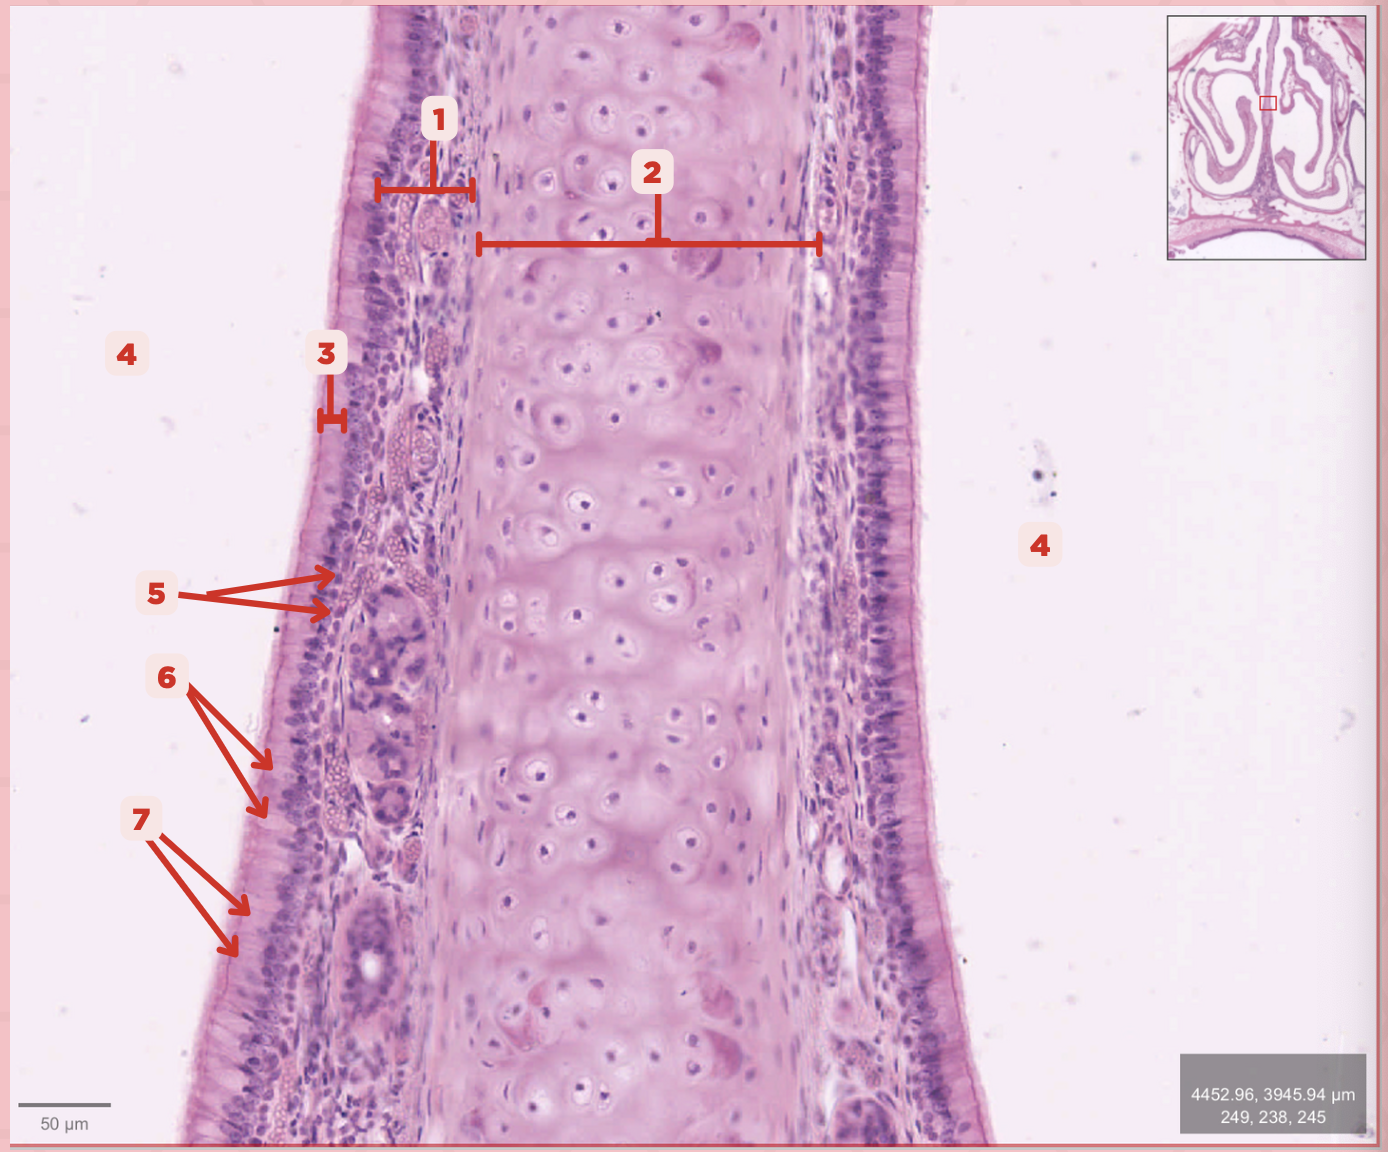

What type of cells make up #1?

Lamina Propria

Identify the structure labeled as 1.

Hyaline Cartilage

Identify the structure labeled as 2.

Respiratory Epithelium

Identify the structure labeled as 3.

Nasal Cavity

Identify the structure labeled as 4.

Basal Cells

Identify the structure labeled as 5.

Goblet Cells

Identify the structure labeled as 6.

Ciliated Columnar Cells

Identify the structure labeled as 7.

Adipose tissue

What type of tissue is sometimes seen between the bony spicules?

Serous and Mucous Glands

What glands are present in the Lamina Propria?